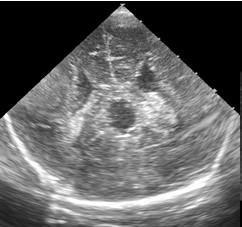

Nace recién nacido de 34 semanas de edad gestacional (EG) con un peso adecuado. A las 31 semanas de EG se observa en la ultrasonografía prenatal una disgenesia de cuerpo calloso asociada a pies equinovaros bilaterales, se realiza RM fetal que confirma la disgenesia con escaso desarrollo de la parte posterior y descarta otras anomalías a nivel intracraneal, el estudio Array-CHG fue normal y se descartaron infecciones en liquido amniótico. El estudio genético mostró un cariotipo 46 XY. El parto fue eutócico. La prueba de Apgar: 9/10/10. pH arteria umbilical: 7,27. No requirió reanimación. En la USC postnatal, se aprecia ( Figuras 1A y 1B).

La sección coronal y parasagital media de la USC muestran un cavum velum interporsitum (CVI) de gran tamaño que en la época fetal dificultó visualizar la parte más posterior del CC (esplenio). La asociación de disgenesia de CC y la deformidad extrínseca (pies equinovaros) que presentaba nuestro paciente dio pié a realizar un estudio genético prenatal por la posible asociación con un síndrome polimalformativo.

Figura 1B US. Corte parasagital